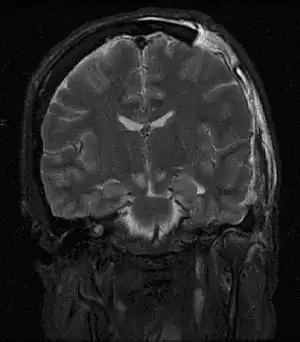

| MRI showing injury due to brain herniation | |